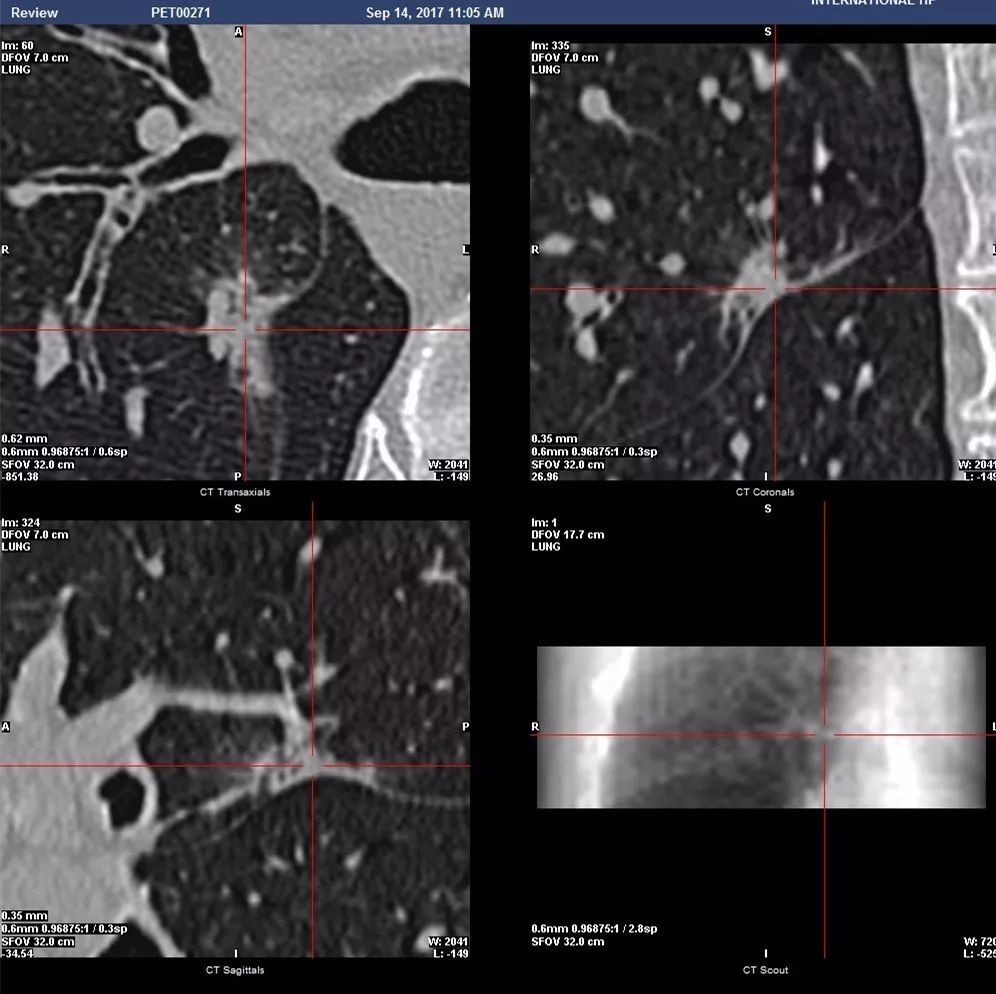

2017年9月14日PET-CT全身检查及病灶局部CT靶扫:左肺上叶后段GGO,FDG轻度摄取,SUVmean=0.6,SUVmax=0.8(图2、3)。病灶大小约1.1×1.8cm,边缘不光整,可见毛刺,内部密度不均匀,其内小支气管受侵管壁增厚扩张并形成空泡,肺间质受侵出现实变影(图4、5)。诊断:考虑为微浸润或浸润型腺癌可能大。